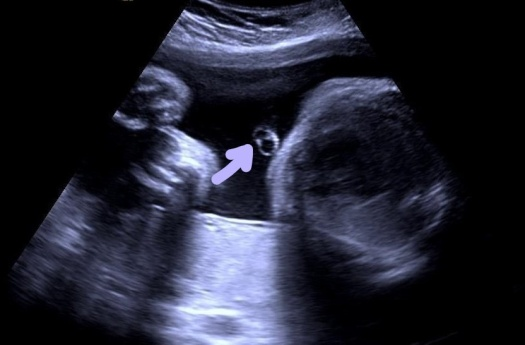

脐带由两条脐动脉和一条脐静脉组成的正常“品”字结构消失,而由仅含一条脐动脉和一条脐静脉组成处“吕”字所取代

众所周知,脐带是连接胎儿与胎盘之间的重要生命通路,正常胎儿脐带内有2条脐动脉及1条脐静脉,起到运送代谢废物和营养物质的作用。而单脐动脉,顾名思义,脐带内只包含1条脐动脉和1条脐静脉。

随着产前检查系统的规范化及超声技术的不断发展,彩色多普勒超声检查已经成为临床诊断单脐动脉的首选方法,并可同时检查发现有无其他结构异常。因此,规范、系统的产前超声检查是出生健康宝宝的重要保障。